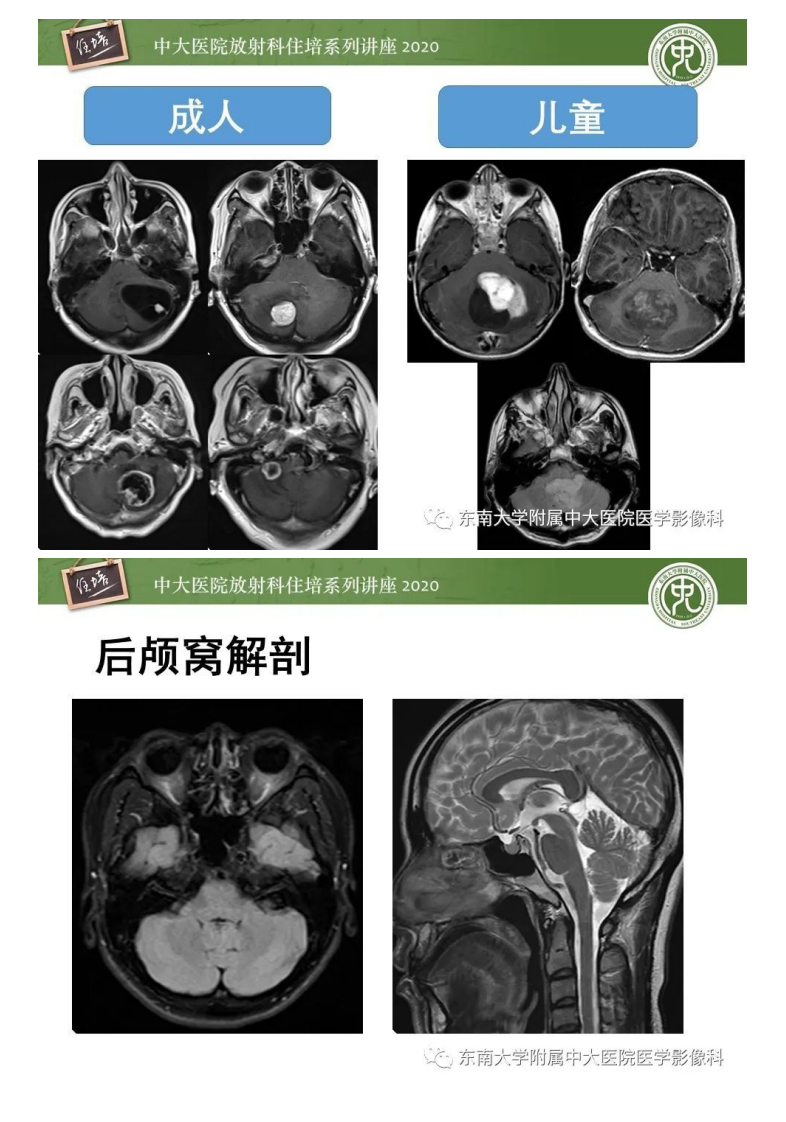

20200510_1【中大放射住培系列讲座】小脑占位的影像分析思路.pdf